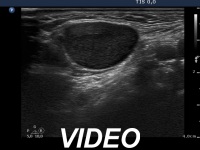

Clinical data: An 80-year-old woman was referred for evaluation with the suspicion of thyroid carcinoma. She noticed a lump in the right submandibular area 3 months ago. The lesion increased slowly over this period. A hypoechogenic nodule with microcalcification was found on neck and thyroid ultrasonography.

Ultrasonography. There was a hypoechogenic nodule presenting microcalcification in the ventromedial part of the right lobe. Corresponding to the palpable mass in the right submandibular area, a lymph node was found. The node did not present hilum.